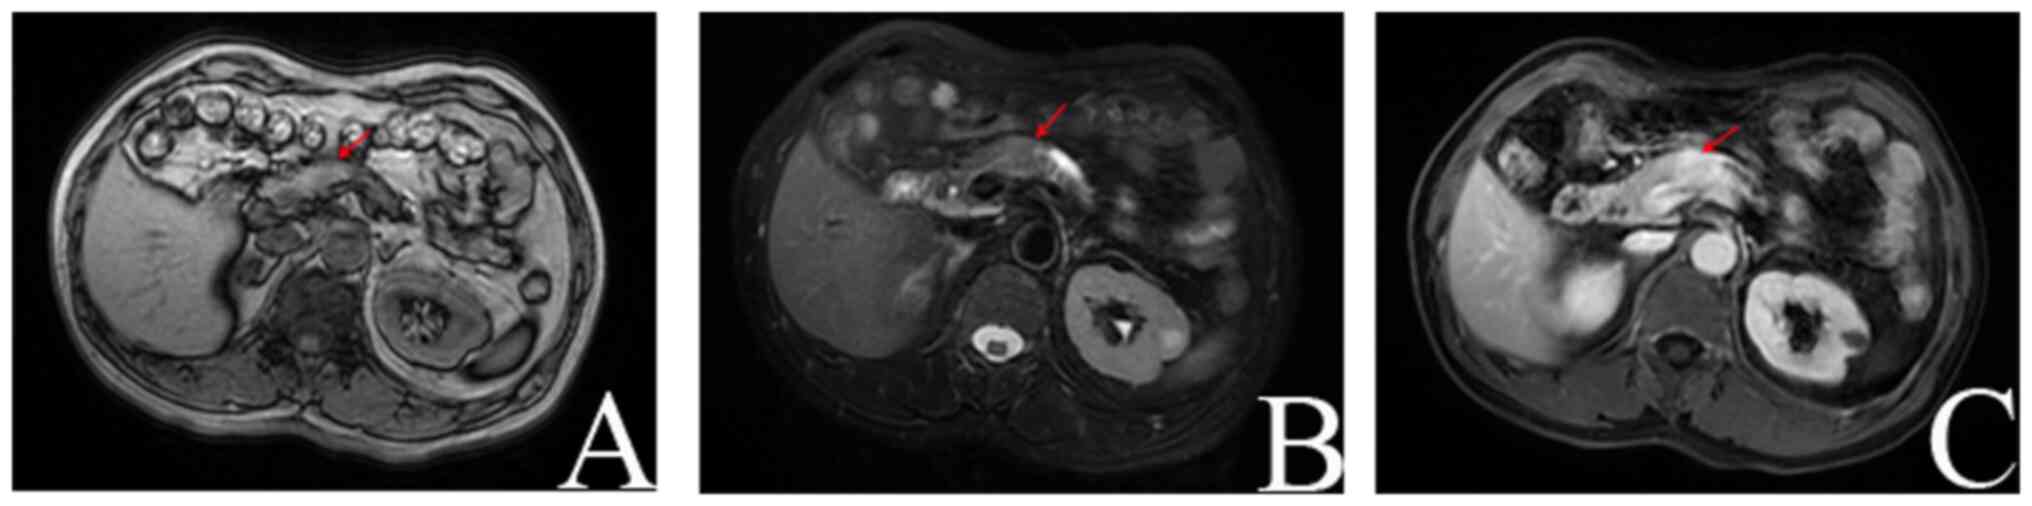

Following this, the patient was transferred to the hepatobiliary surgery department of the same hospital for further evaluation; subsequently, a comprehensive examination using a hepatobiliary 1.5T magnetic resonance imaging (MRI) protocol was conducted. This imaging protocol included plain scans, diffusion-weighted imaging and enhanced scans. The MRI findings revealed the presence of a space-occupying lesion in the pancreatic body, indicative of pancreatic cancer. Additionally, atrophy was observed in the distal body and tail glands of the pancreas, accompanied by pancreatic duct dilation. Furthermore, the examination revealed multiple cysts in the liver with bilateral renal cysts observed, bilateral renal cysts have no pathological concern (Fig. 2). Diagnoses of a pancreatic space-occupying lesion in the pelvic space, a hepatic cyst, a renal cyst and a right ureteral calculus with hydronephrosis were made. A definitive diagnosis was ascertained for the patient following a multidisciplinary expert consultation and the evaluation indicated the presence of a space-occupying lesion in the pancreas, raising concern for possible pancreatic cancer. The presence of a pancreatic tumor could not be conclusively ruled out at this stage and additionally, a space-occupying lesion in the pelvic region was identified, warranting further investigation. Moreover, the expert consultation considered the possibility of a small GIST being present. Surgery was deemed the most appropriate primary treatment for pancreatic cancer with the aim to remove the tumor, and keep the biliary and pancreatic ducts unobstructed. General anesthesia was used in this case as in accordance with more extensive operations in similar cases.

Figure 2.

Hepatobiliary 1.5T magnetic resonance plain scan, diffusion weighted imaging and enhanced scan. (A) T1WI pancreatic cancer, (B) T2WI pancreatic cancer, (C) delay period, pancreatic cancer. T1WI, T1-weighted image; T2WI, T2-weighted image. The red arrows indicate the location of the lesion.